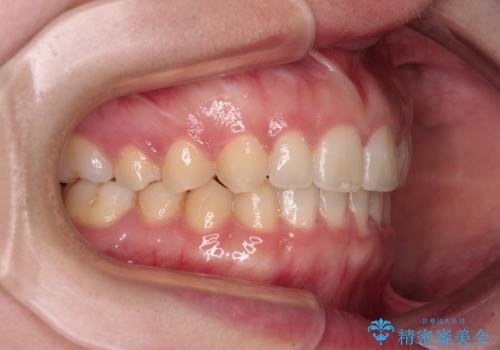

気になる残存乳歯と八重歯 ワイヤー矯正を併用したインビザライン治療

- 八重歯を気にして来院された患者様です。

八重歯のために乳歯が残存していたため、乳歯を抜去して八重歯となっている犬歯を歯列に収めることとしました。

八重歯の移動量が多くなるため、インビザラインと併用してワイヤー矯正を行い、八重歯を改善した後に、上下歯列をインビザラインで整えることとしました。

犬歯は歯根が長くて太いため移動に時間がかかる上に、周囲の歯が八重歯に寄ってきてしまうため、仕上がるまでに期間がかかりました。